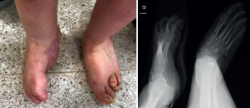

Además, se observa una normalización del ángulo de Meary y el de Costa-Bartani (Figura 5).

Figura 5. Radiografías en carga que muestran la normalización de los ángulos de Meary y Costa-Bartani.

El valor normal del ángulo de Meary sería menor de 10° y nos sirve para evaluar la alineación del arco longitudinal medial del pie y cuantificar deformidades sagitales(11).

El valor normal del Costa-Bartani es entre 120 y 130°, y evalúa la altura y la estabilidad del arco medial, y el equilibrio estructural del pie(12).